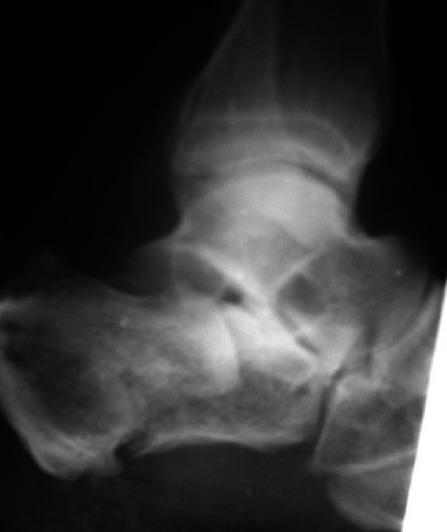

Calcaneal fracture, the most common tarsal bone fracture, occurs predominantly in manual labors and subsequently has got considerable socioeconomic implications. Treatment modality which can offer early weight bearing and early return to work is therefore needed for those patients. We have used a biplanar percutaneous external fixator for treating calcaneal fractures without operative and per operative visualization of the fractures. We have treated 17 calcaneal fractures in 16 patients, 12 intra articular and five extra articular, with our percutaneous external fixator system without preoperative X-ray control or reduction. Functional outcome was measured using the American Orthopaedic Foot and ankle society Hind foot score. All fractures united with a mean of 55 days. Partial weight bearing was possible in a mean of 1.8 days and full bearing was possible in a mean of 11.6 days. All the patients were returned to their original work within six weeks. Minor infectious complications occurred in 17.6 percent of cases. The average AOFAS score at six months follow up was 83.8. We conclude that our percutaneous external fixator technique for fracture calcaneum is an effective alternative to the currently available - surgical and conservative treatment modalities especially in lower socio economic labor population who need to return to their job as early as possible. Level of Evidence - IV Case series.